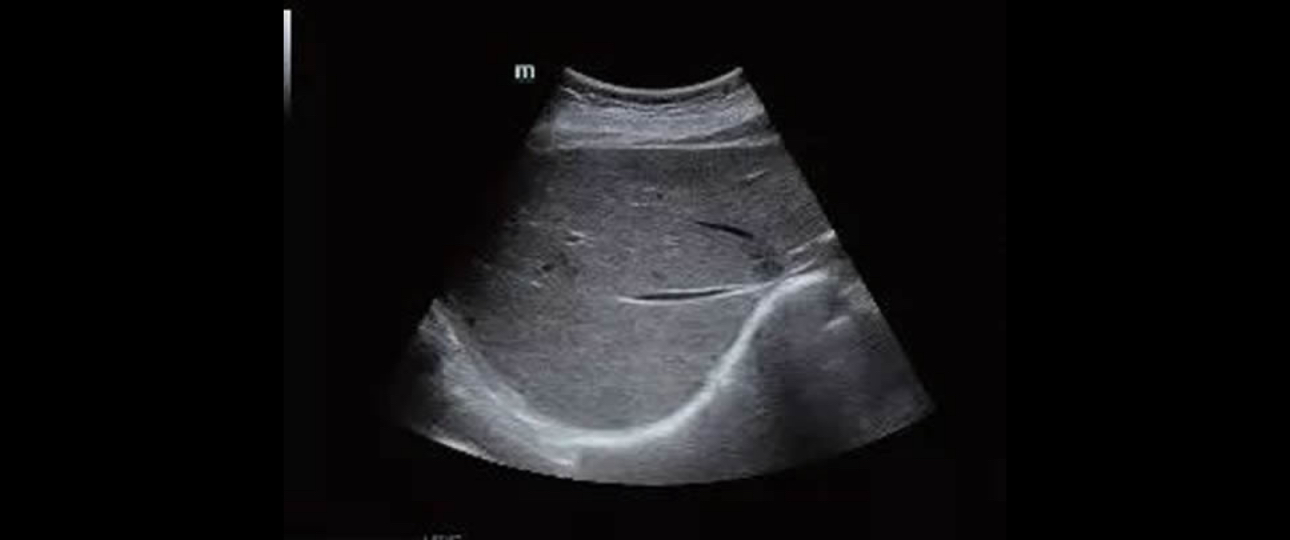

To better understand his condition, the team progressed into a non-invasive, rapid and accurate method, the ultrasound examination.

To their surprise, a bright liver with smooth margins and patent portal vein has been found using the B-mode and Doppler of Mindray’s Resona 7. Moreover, the mean portal blood flow velocity was 28 cm/s and the flow in the hepatic veins had a biphasic pattern.[2]

B-mode findings - a bright liver with smooth margins

Doppler findings - flow in the hepatic veins has a biphasic pattern